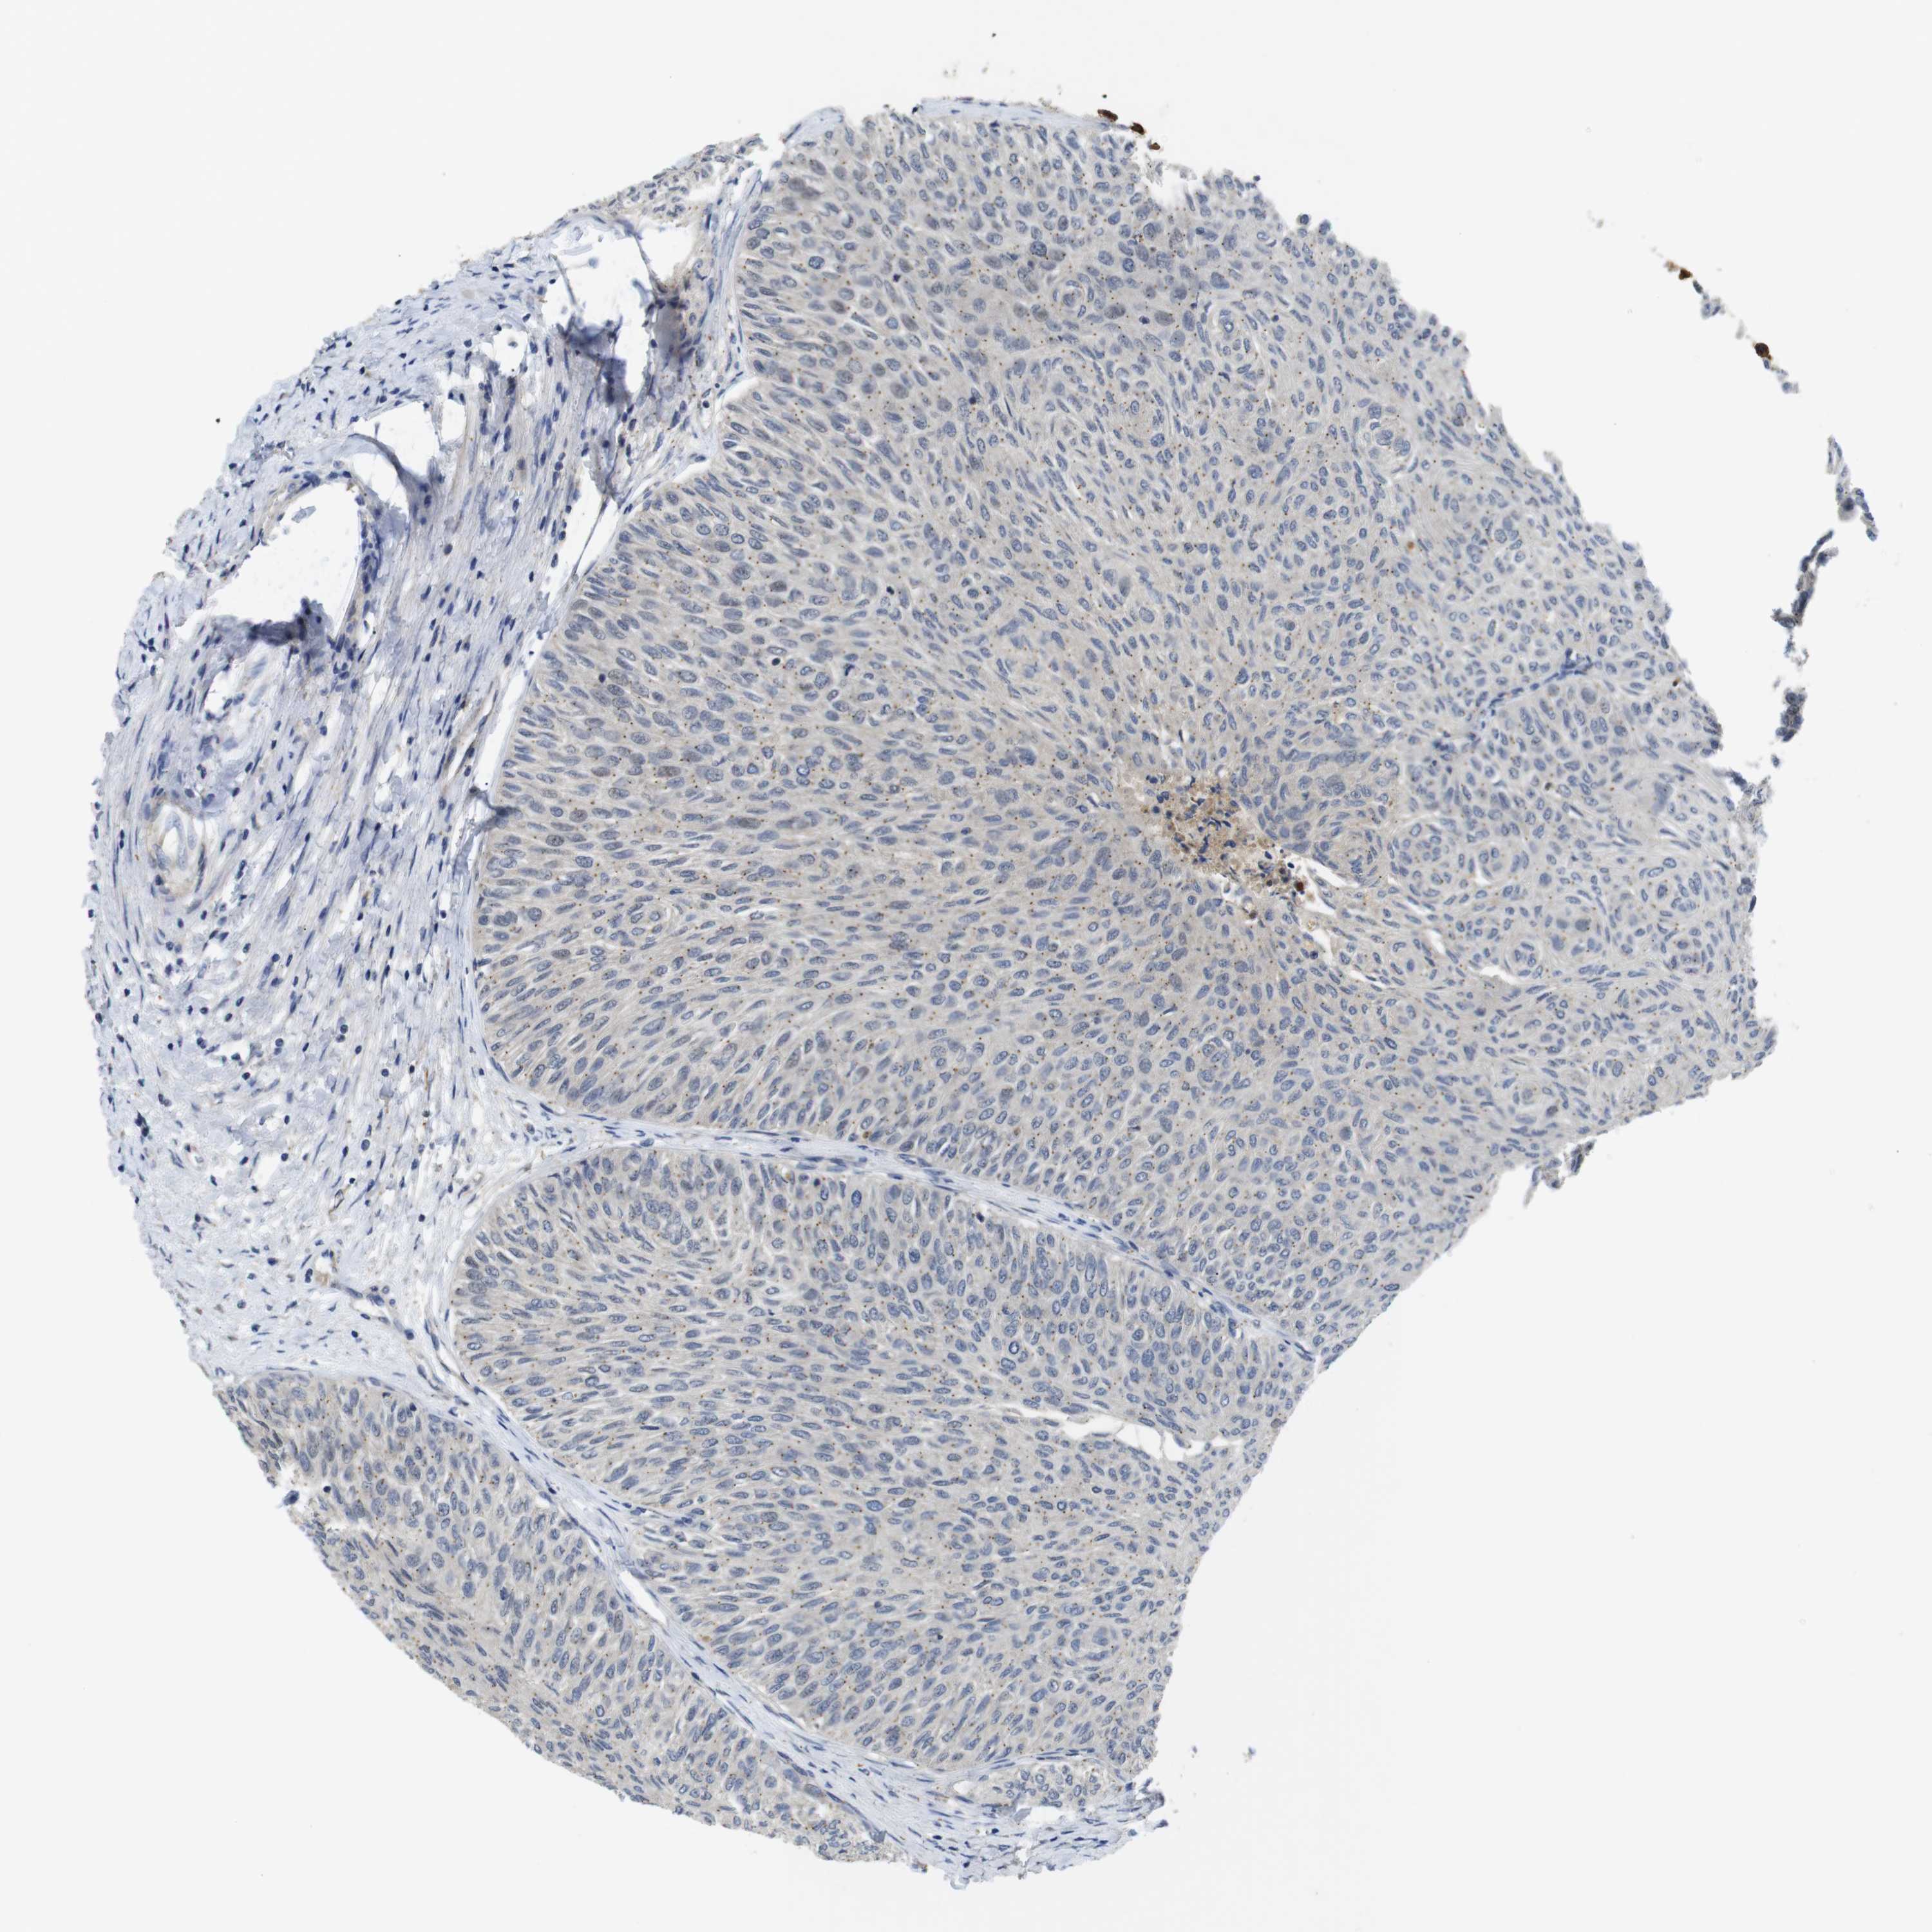

UROTHELIAL CANCER - Protein expressioni

A mouse-over function shows sample information and annotation data. Click on an image to view it in a full screen mode. Samples can be filtered based on level of antibody staining by selecting one or several of the following categories: high, medium, low and not detected. The assay and annotation is described here.

Antibody stainingi

Antibody staining in the annotated cell types in the current human tissue is reported as not detected, low, medium, or high, based on conventional immunohistochemistry profiling in selected tissues. This score is based on the combination of the staining intensity and fraction of stained cells.

Each image is clickable and will lead to virtual microscopy that enables deeper exploration of all samples and also displays staining intensity scores, fraction scores and subcellular localization as well as patient and tissue information for each sample.

Antibody HPA018830

Antibody CAB010149

Urothelial carcinoma, Low grade

Urothelial carcinoma, High grade